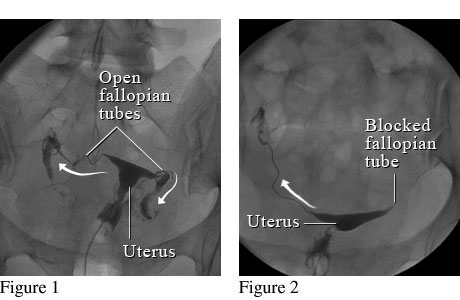

사진을 보면 더 정확하게 알 수 있습니다.

사진을 보시면 자궁경부 입구  주사기 안에 들어 있는 조영제를 순차적으로 점점 밀어 넣게 됩니다.

그래서 만일 나팔관이 막혀 있지 않다면 자궁안을 채우고 난 이후 나팔관으로 순차적으로 조영제가 빠져 나가는 것이 확인이 되겠지만, 만일 자궁에 혹이 있는 경우엔 그 부분이 검게 뚫어져 있을 것이고, 나팔관이 막혀 있다면 나팔관 바깥쪽으로 조영제가 빠져 나가질 않을 것입니다.

그림1. 정상 나팔관 모습          그림2. 한쪽 나팔관이 막혀 있는 모습